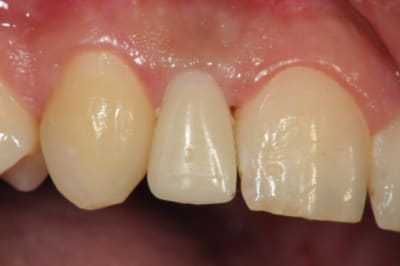

je reviens sur ce cas que j'ai un peu délaissé...

il est terminé, j'ai juste oublié de mettre la suite.

-cicatrisation

-mise en place vis de cica petit diamètre

-ensuite on augmente le diamètre en conservant et en gonflant les tissus gingivaux

-cicatrisation de la première vis de cica,

-diamètre plus gros pour la vis de cica

- pilier pour la provisoire

- provisoire moule ION

- ajustage

- polissage soigneux

la suite tout à l'heure, ça sonne à la porte...